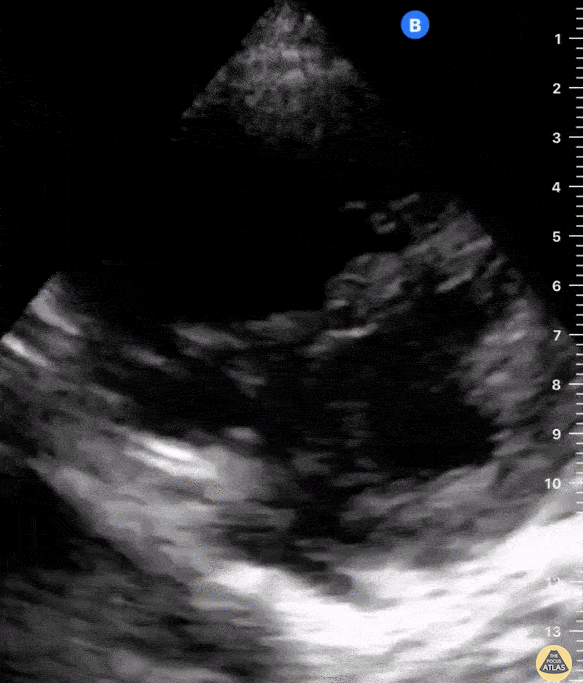

Equality: is the RV dilated or significantly impaired?

Normally, the RV is a low-pressure, thin-walled, high-compliance chamber that wraps anteriorly around the muscular, cone-shaped LV. The normal RV : LV diameter ratio is 0.6 : 1.

When the pulmonary artery pressure rises, the RV will dilate, altering the normal RV:LV ratio. Although sacrificing sensitivity, the use of equality (1:1 ratio) as a cutoff can achieve a specific estimation of RV strain. If imaged correctly by a trained operator, the presence of an RV:LV ratio > 1 is highly specific for RV strain.

RV dilation can be acute, chronic, or acute-on-chronic. However, in patients presenting with undifferentiated chest pain, shortness of breath, hypotension or syncope, the presence of any RV dilation should raise suspicion for acute pulmonary embolism (PE). Furthermore, in a patient in shock, the presence of RV strain may signal the need for aggressive therapy – emergency thrombolysis.

THE VIEWS

The A4C view provides an accurate chamber size comparison. However, achieving a proper A4C view (avoiding foreshortening or ballooning, and visualising the four chambers with a vertically oriented interventricular septum) can be a challenging exercise of image acquisition. Additionally, the PSAX view at the level of the papillary muscles shows both LV and RV side by side and is useful to assess function and size. When RV pressure is high, the septum will be pushed and flattened towards the LV, resulting in the characteristic “D-shaped” LV or “D sign”.